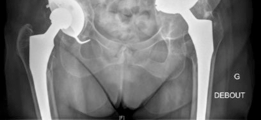

8. Final Stability Assessment and Closure:

A final assessment of hip stability was performed. Full range of motion was demonstrated without impingement or dislocation. Leg lengths were re-evaluated and corrected to within 0.5 cm of the contralateral side. The surgical wound was irrigated extensively, a drain was placed, and the deep fascia, abductor muscles, and subcutaneous layers were meticulously closed in layers.

![Image](/media/upload/1af68bbe-ecf1-4af4-8279-9350a3982c00.png)

This image likely represents the immediate post-operative radiograph, clearly demonstrating the Burch-Schneider cage in situ, the cemented polyethylene liner, and the well-positioned femoral stem, with initial bone graft material visible.

![Image](/media/upload/144b8a61-27c8-48c3-b82f-249a148daaf0.png)

This image likely depicts a follow-up radiograph, showing continued good position of the components and signs of early bone graft incorporation, or potentially a different projection to confirm cage integrity.